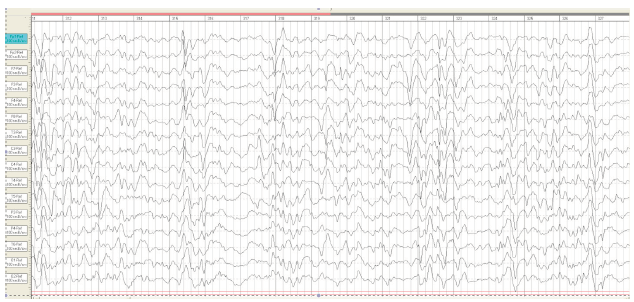

On the 6th day, the first generalized epileptic seizures developed without apnoe. From the age of 1-month myoclonic jerks and generalized tonic clonic seizures were continued. Video- EEG recording at the age of 1 month on EEG slow background activity with tiform activity “sharp slow wave” with periods of depression rhythm (Burst suppression patterns) (Figure 2). Taking into consideration the clinical picture of seizures and EEG data, the child was diagnosed «Infant epileptic encephalopathy Syndrome Ohtahara. On EEG at the age of 2 months the deterioration of the background rhythm, the increase in the index of epileptiform activity, hypsarrhythmia (Figure 3).

Figure 2:EEG M.R., 1 month. Burst suppression pattern.

Figure 3:EEG M.R 2 month. Modified hypsarrhythmia..

Even though existing antiepileptic drugs namely valproic acid, levetiracetam, lamotrigine, clonazepam, vigabatrin, seizures were continued and by 7 months were transformed into infantile spasms with registration of hypsarrhythmia on EEG (Figure 6). Thus, the child recorded the transformation of Otahara syndrome into West syndrome. From the age of 12 months, multifocal epileptic activity was registered on the EEG (Figure 7). By the age of 1.5 years, the boy develops with the global delay. Convulsive syndrome persists in the form of jerks involving the muscles of the face; spasms and focal sizures. Improvement of the condition was achieved with the appointment of levetiracetam, clonazepam, lamotrigine. The fundus of the eye revealed optic nerves atrophy.

Figure 6:Boy, 7 months. EEG–the pattern of hypsarrhythmia.

Figure 7:Boy M.R., 12 months. EEG multifocal epileptic activity.

Since the neonatal period, epilepsy resistant to therapy developed. By the age of 7 months-complex partial and jerk events transformed into infant spasms. pattern of hypsarrhythmia was registered on the EEG. From the age of 12 months, according to the criteria of ILAE, a pattern of multifocal epileptic activity was registered, “resistant to treatment of epilepsy” was confirmed. At the age of 7 months-West syndrome was registered and to 1 year of life Markland-Blume-Otahara syndrome (multifocal epilepsy) was proposed. Just now the boy is 1,5 years old. Profound developmental delay was developed- significantly delayed in the cognitive and physical development: delayed in motor skills, speech, cognitive skills, and social and emotional development. On examination, the myoclonus appears at rest, on keeping in day time and to look for the stimulus sensitivity and related to focal myoclonus that occurs in symptomatic epilepsy, in the setting of infection, inflammation, vascular disease, trauma or tumors. Epileptic spasms persist up to 5 times a day.